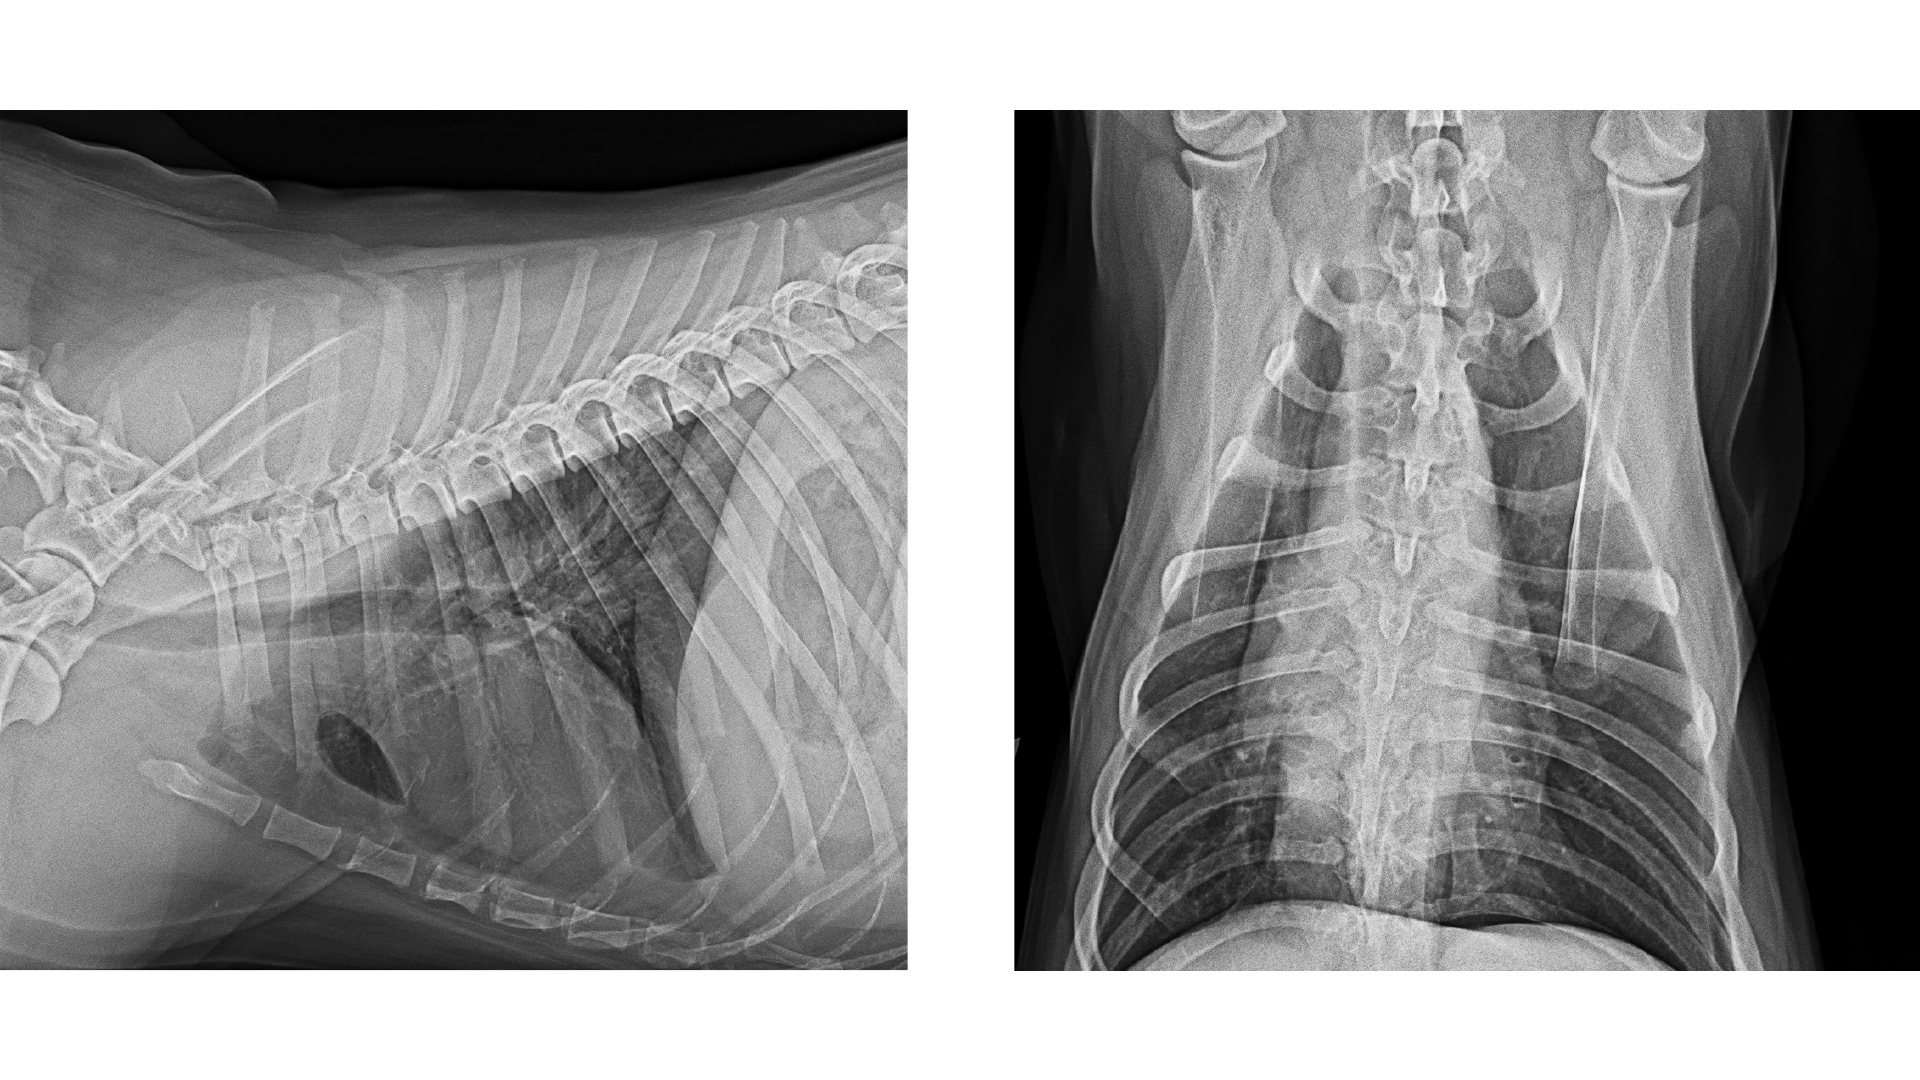

Bei der Blutchemie waren alle untersuchten -Organwerte in der Norm. Das Blutbild zeigte einen normalen Hämato-krit (42 Prozent), eine Thrombozytopenie (69 K/µL), eine Retikulozytose (137 K/µL) und eine Leukozytose (27 K/µL) mit Neutrophilie und Monozytose. Das C-reaktive Protein (CRP) war mit 162 mg/l (0–10) deutlich erhöht. Die Thrombozyten von Akiro wurden bereits bei vorhergehenden Untersuchungen mittels Blutausstrich kontrolliert und als Megathrombozyten und demnach als nicht pathologisch diagnostiziert. Die Röntgenuntersuchung des Thoraxes in zwei Ebenen erschien unauffällig (Abb. 1), wohingegen der Ultraschallbefund deutliche Veränderungen zeigte. Neben einem mittelgradigen Aszites war im kaudalen Abdomen eine circa sechs Zentimeter große, runde, inhomogene Masse mit gemischter Echogenität zu erkennen (Abb. 2). Dem ersten Anschein nach handelte es sich um eine Umfangsvermehrung der Milz, allerdings war keine Verbindung zu dieser auszumachen. Die restlichen Bauchorgane konnten gut abgegrenzt werden und zeigten sich sonographisch unauffällig. Das Punktat der freien Flüssigkeit war sero-sanguinös mit einer hohen Zellzahl und hohem Eiweißgehalt von 4,5 g/dl (Abb. 3). Demnach handelte es sich um ein Exsudat. Das zytologische Bild des Punktats zeigte eine sterile Entzündung. Der Hämatokrit des Punktats war bei zwölf Prozent.